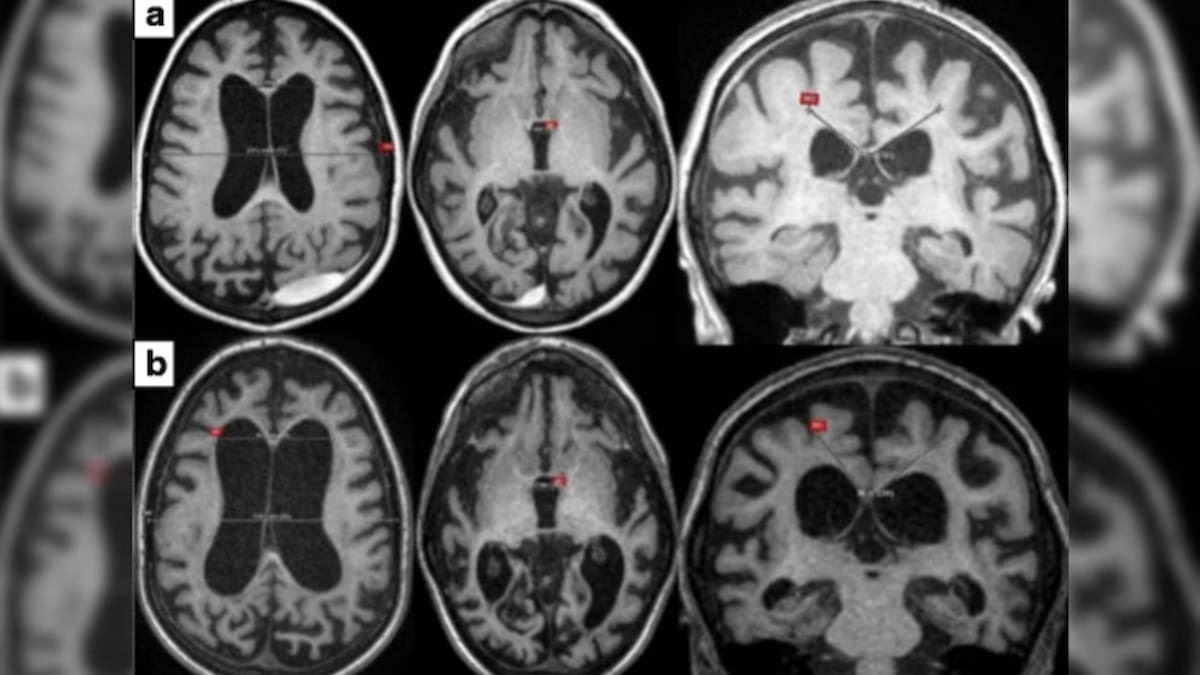

EEUU — La Administración de Alimentos y Medicamentos aprobó el medicamento Avlayah, una terapia innovadora diseñada para tratar el síndrome de Hunter, una afección que provoca deterioro neurológico progresivo en niños.

Se trata del primer avance en más de 20 años con capacidad de impactar directamente el cerebro, mediante un esquema de aprobación acelerada.

El nuevo medicamento logra atravesar la barrera hematoencefálica, lo que permite actuar directamente en el sistema nervioso central.